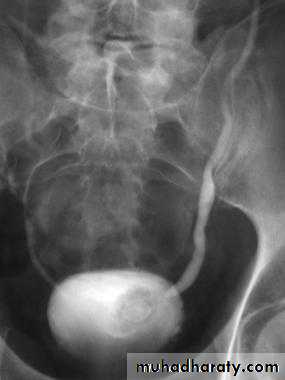

Bilateral ureteroceles. dilatation of the distal ureter as it enters through the bladder wall. This produces a typical “cobra head” deformity (arrows.